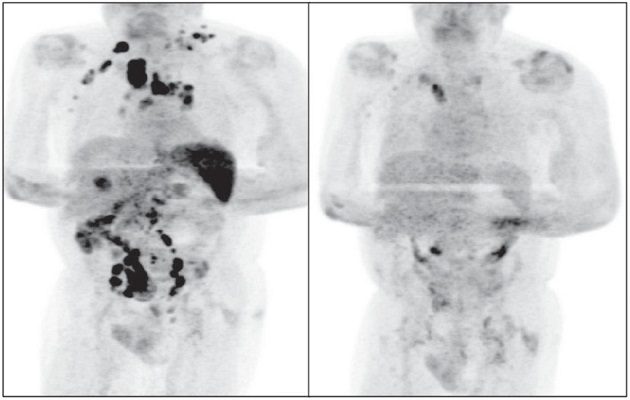

Cuatro meses después, la inflamación de los ganglios se había reducido y una exploración PET reveló una remisión generalizada del linfoma.

De acuerdo con los autores de la publicación, que detalla The Conversation y la BBC, la hipótesis es que la infección por SARS-CoV-2 desencadenó una respuesta inmunitaria antitumoral: las citocinas inflamatorias producidas en respuesta a la infección podrían haber activado células T específicas con antígenos tumorales y células asesinas naturales contra el tumor. El SARS-CoV-2 le habría curado el linfoma.